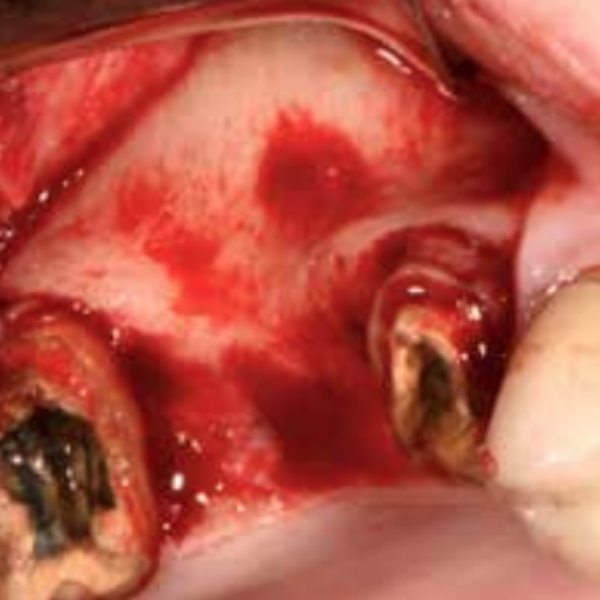

UL5 Extraction and Implant Placement

Patient suffered from a root fracture. Needed removal and to restore hard and soft tissue.